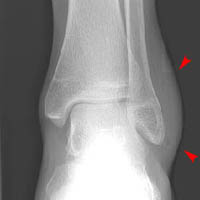

Now look at the radiographs below. Does this patient have a fracture?

Click on the image for the answer.

Mortise and lateral views of ankle